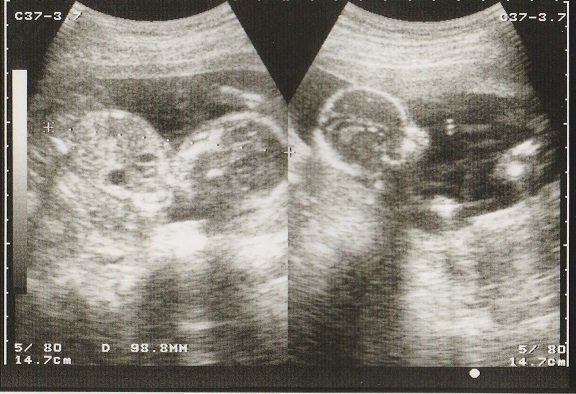

つぼいみきさんの妊娠16週目のエコー写真 性別が判明

性別が判明

左写真では目や口元がわかり、顔がちゃんと確認できます。右写真は足がうつっています。足の間が開いた状態であったため、これを見て先生は「今のところ女の子だね」と性別を教えてくれました。夫婦ともに第1子は女の子を望んでいたため、大喜びでした。また、妊娠が発覚してから悪阻もないのに私の体重が全く増えておらず、赤ちゃんがちゃんと育っているのかが不安でした。先生から「赤ちゃんは正常だから大丈夫。お母さんの体重も5ケ月を過ぎた頃から増え始めることもあるから心配しないで」と言われ少し安心しました。